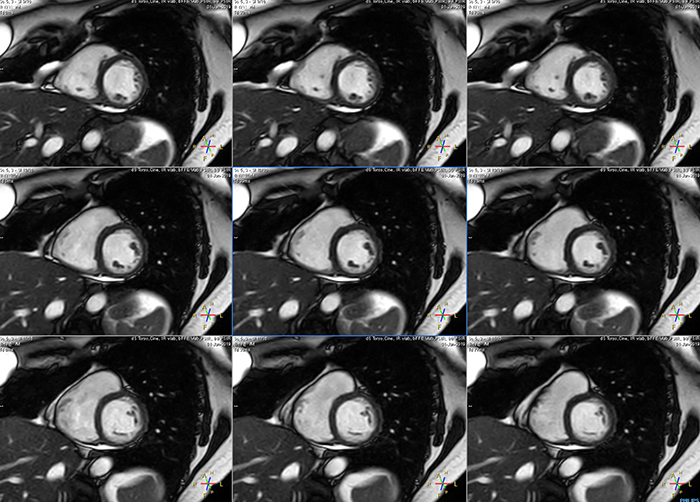

Avila says that Compressed SENSE allows them to reduce breathhold time to 3 to 4 seconds in cardiac cine scans. “At the same time, we can now – based on cardiac frequency – obtain as many as 30 to 40 cardiac phases without sacrificing resolution, while before Ingenia Ambition, we were acquiring only 20 phases.

“This ability to use Compressed SENSE for obtaining higher temporal resolution translates to a much smoother cine. This allows me to better assess heart function,” Dr. Peña says.

The images obtained with Ingenia Ambition show large coverage and high uniform signal. More vessels are visible than in a previous exam of the same patient on Achieva. The movies show a higher temporal resolution in the Ambition acquisition than in a previous Achieva 1.5T exam. Both exams use a FOV of 300 mm and voxel height and width of 0.78 mm.

Achieva 1.5T

2:30 min. TE 1 ms, TR 4 ms

Ingenia Ambition

4D Trak XD 1:54 min. TE 1ms, TR 3ms

The team at Miami Cardiac & Vascular Institute also appreciates Ingenia Ambition’s capabilities for fast dynamic CE-MRA. “With 4D TRAK XD, we get much better temporal and spatial resolution. Previously, with the Achieva we needed 6 seconds per dynamic, but now we can shorten that to 2 seconds per dynamic,” Avila says. “As a result, we can see the transition from arterial to venous phase with much higher temporal resolution. This is important, for example, for imaging arteriovenous malformations, which are quite vascular.”

“On our previous system we really had to sacrifice image resolution to get to 5- or 6-second temporal resolution, while now – using 4D TRAK XD on Ambition – we no longer have to sacrifice image quality,” Dr. Peña says.

These are some images of a cardiac cine scan with a short breath-hold time. A high temporal resolution provides a smooth cine, which helps in assessing heart function. Ingenia Ambition.